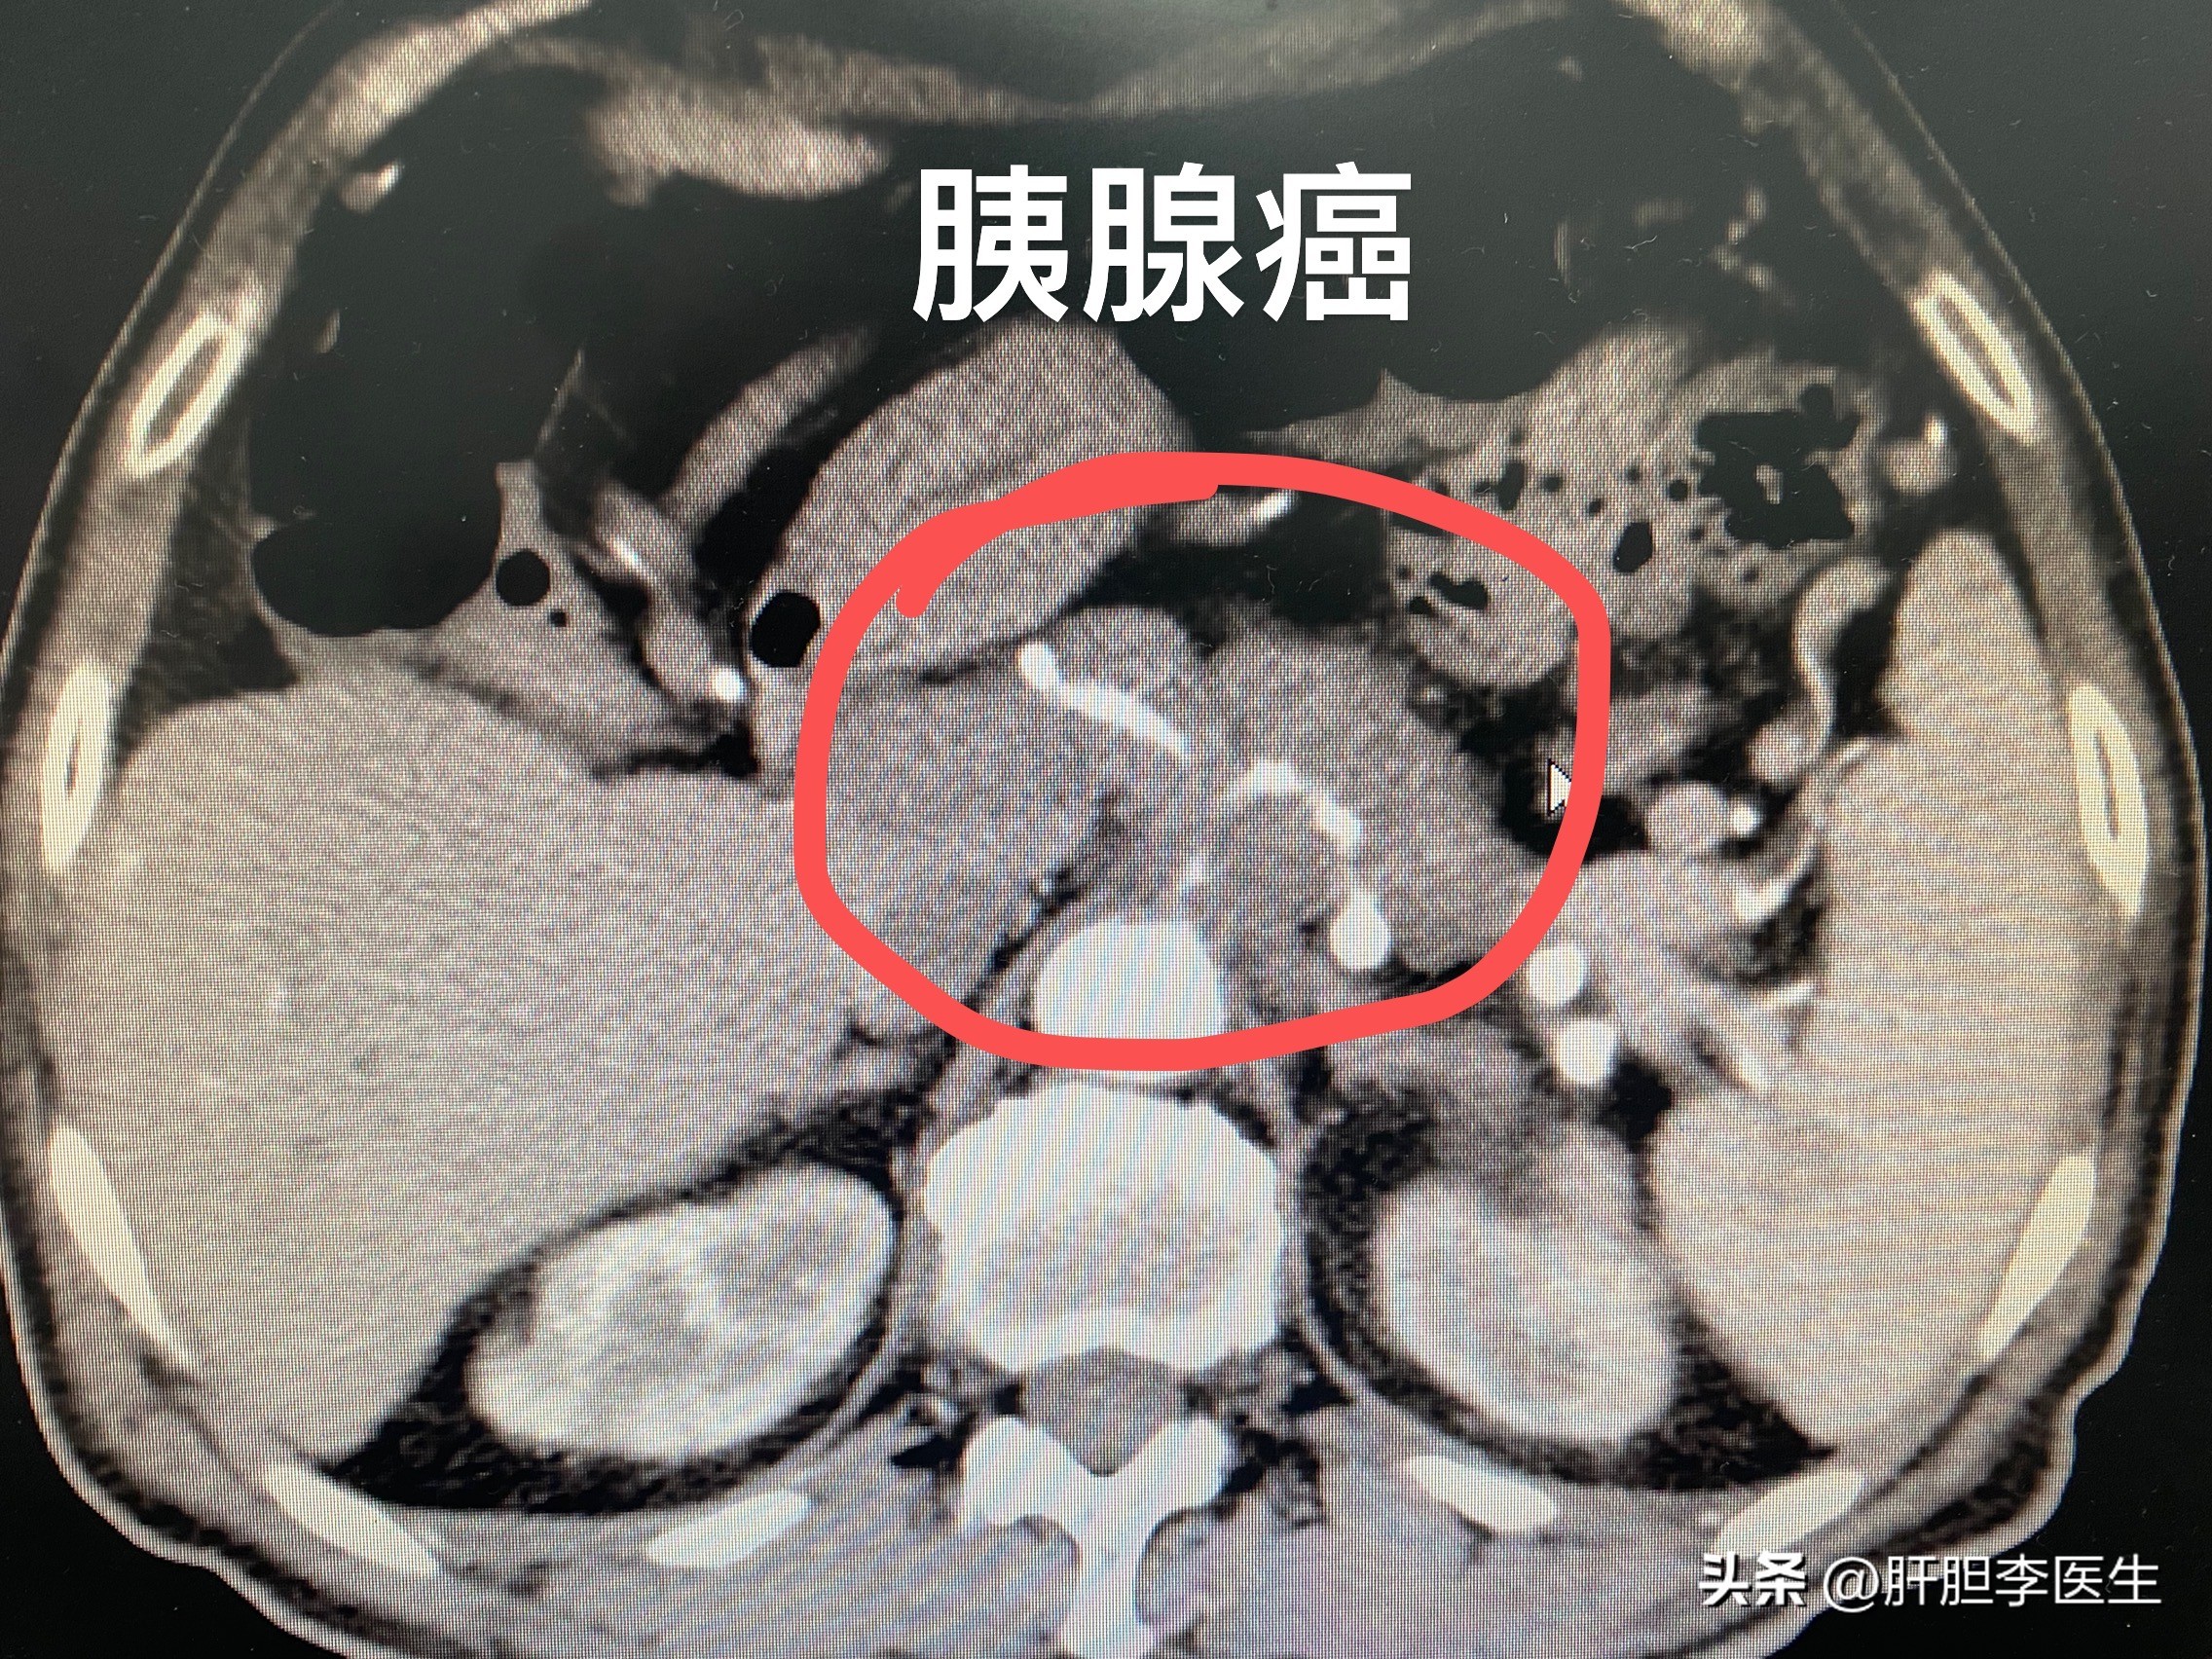

从片子上看,胰体部有一个低密度肿块,肿瘤紧紧的包绕着腹腔动脉以及肠系膜上动脉。最要命的就是肝脏上还有很多转移瘤,几乎占满了整个肝脏,病人的胆红素已经高达400多,达到了肝衰竭的程度了。

很显然,病人已经是胰腺癌晚期了,而且按照这种病情的发展趋势,生存时间不会超过一个月,他的肝功能会在接下来的一个月内迅速恶化,逐渐的进入昏迷状态,然后去世!